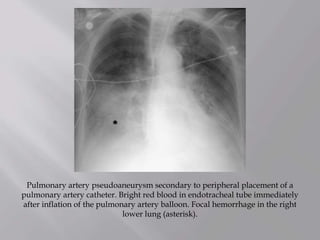

Pulmonary artery pseudoaneurysm secondary to peripheral placement of a

pulmonary artery catheter. Bright red blood in endotracheal tube immediately

after inflation of the pulmonary artery balloon. Focal hemorrhage in the right

lower lung (asterisk).